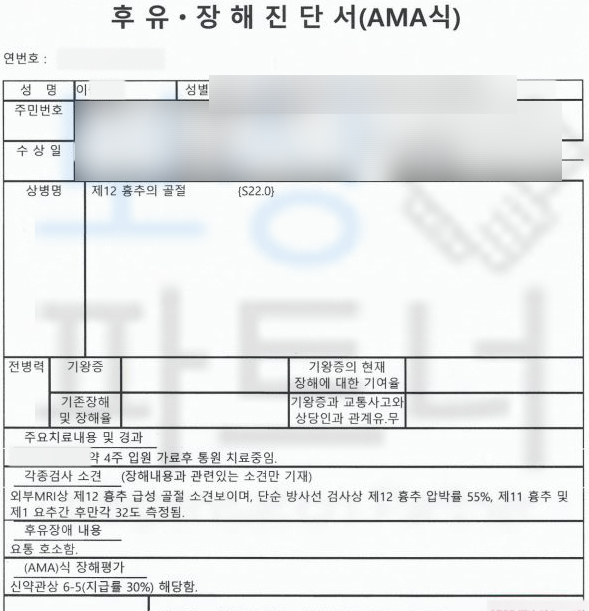

12번 흉추의 골절 S220

척추는 우리 몸의 중심부로서 골절이 발생하면 향후 각도 변형이나 골절로 인해 척추체의 압박률이 점점 가중되는 후유장해를 유발 할 수 있습니다.

AMA 방식의 후유장해 평가를 진행하였고

무려** 30%의 지급률 뚜렷한 기형**에 해당하셨습니다. 저희는 이를 기초로 손해사정서와 각종 증빙서류를 제출하였습니다. 물론 보험사에서는 이전의 질병들을 조회하며 골다공증의 여부와 각도와 압박률의 적절성에 대해 의료자문을 시행했지만 보상파트너의 적절한 대응으로 결국 저희가 처음 청구한 30% 지급률 인정되어